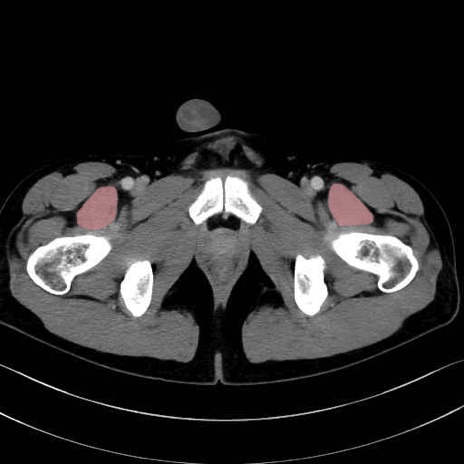

梨状筋 (Piriformis)

内閉鎖筋 (Obturator internus)